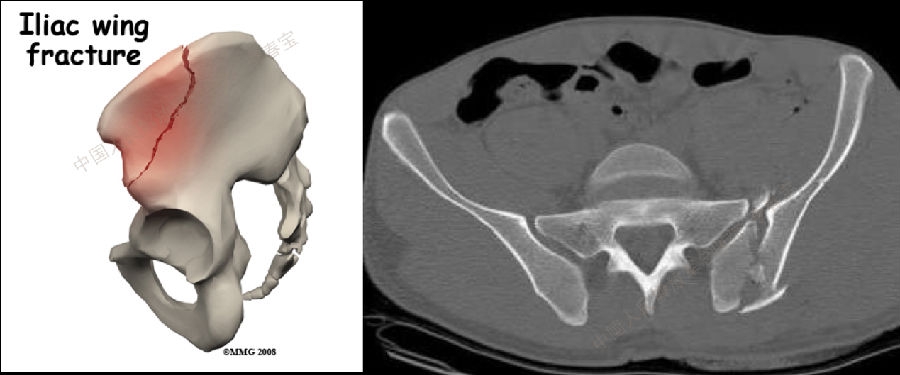

3. 髂骨翼损伤

此种损伤在马术运动中最易发生且损伤严重。骨折后出现剧烈疼痛,局部压痛,但患者多拒绝按压局部,有时出现腹部和臀部不自主的肌肉的痉挛。向患侧旋转45°骨盆X片片可以确诊。治疗:卧床6-8周多可愈合。